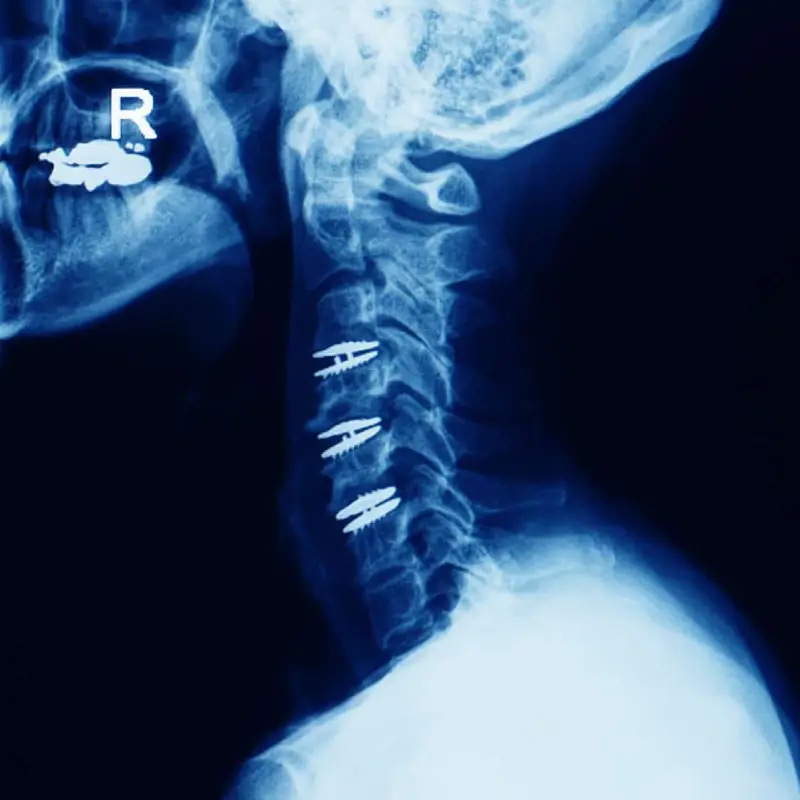

Anterior Cervical Discectomy And Fusion With Plating